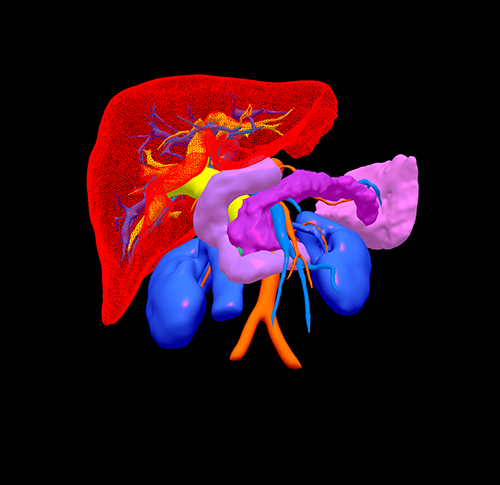

胰头癌-胰十二指肠切除